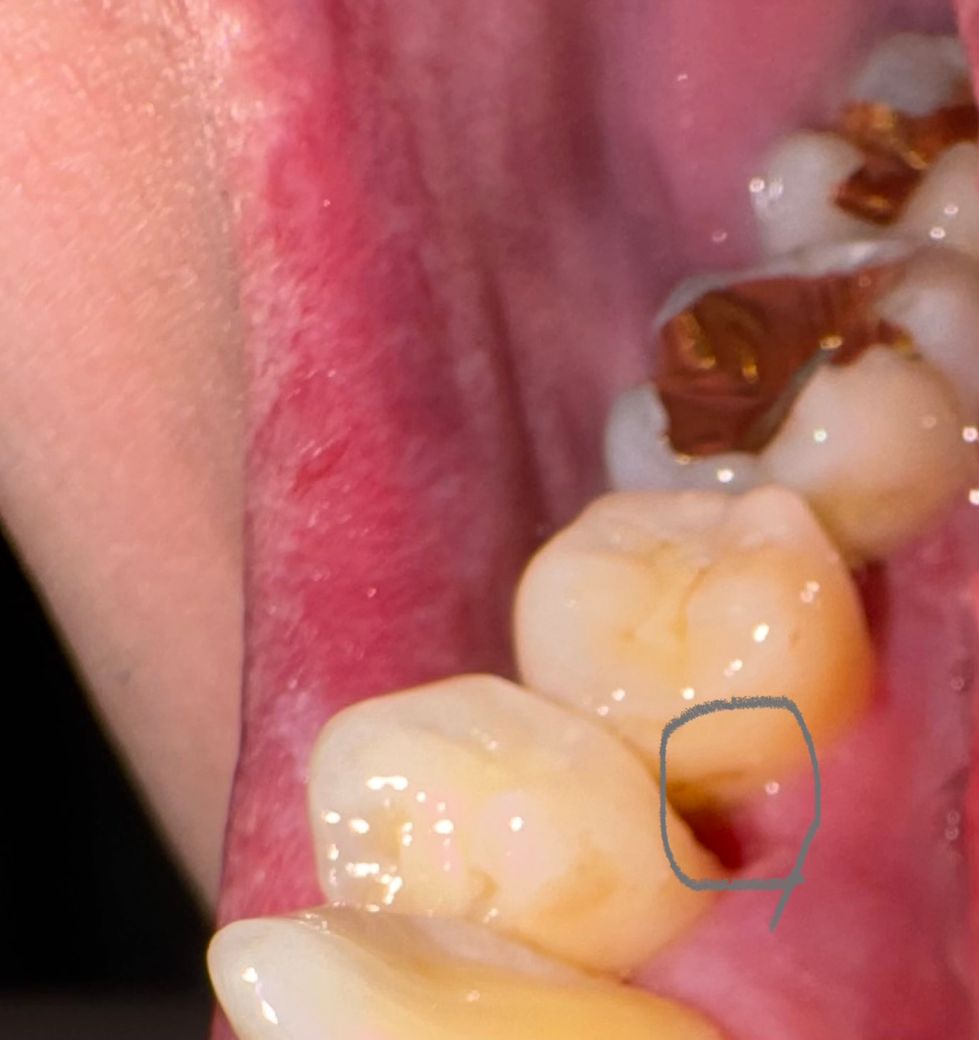

잇몸치료를 하고 왔는데요 잇몸 파인부분 재생기간이 궁금해요

화욜날 잇몸이 살짝 불편해서 치과 방문후 엑스레이

촬영후 선생님이 잇몸에 약간의 염증소견이 있다고

잇몸치료를 해주셨는데요 사진 속 부분이 기존에

조금 파여있엇는데 잇몸치료후에 조금 더 범위가

넓어졌는데 치료한 부분

잇몸재생은

기간이 얼마나 걸리나요?

아래치아 안쪽사진입니다.